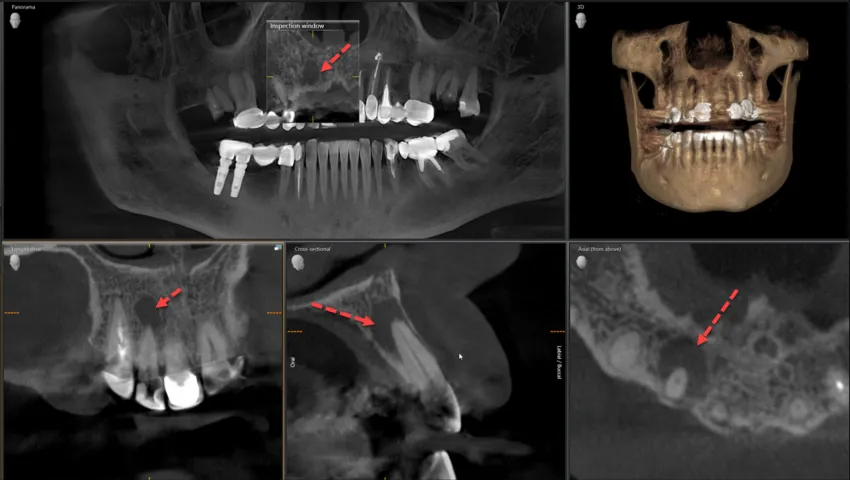

Tomografia CBCT: złoty standard w wykrywaniu pęknięć korzeni

Dlatego też, w przypadku podejrzenia pęknięcia, szczególnie korzenia, tomografia komputerowa wiązki stożkowej (CBCT) jest dla mnie metodą z wyboru. To trójwymiarowe badanie pozwala na uzyskanie niezwykle szczegółowego obrazu zęba i otaczających tkanek, co daje niemal 100% pewność diagnostyczną. Dzięki CBCT mogę dokładnie zlokalizować pęknięcie, ocenić jego głębokość i kierunek, co jest niezbędne do zaplanowania skutecznego leczenia. To narzędzie, które naprawdę ratuje zęby.